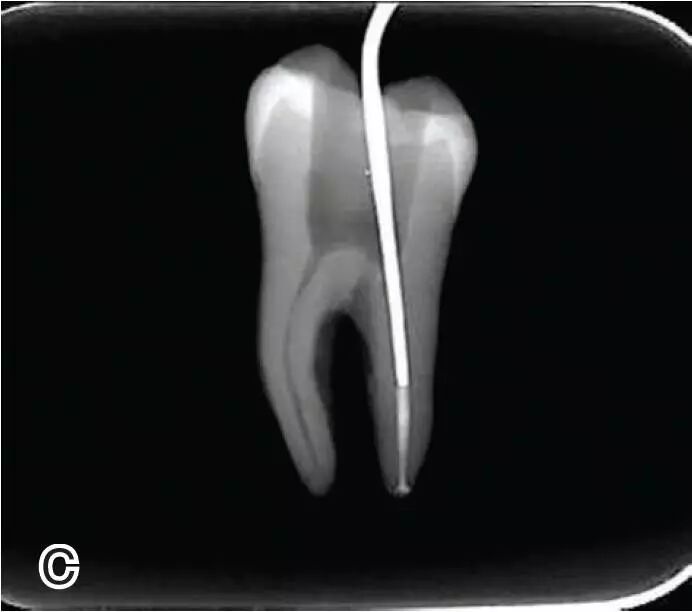

热牙胶根中上段的充填

在完成根尖段的充填后,使用热塑牙胶注射仪对根管中上段进行分层充填,一般分2~3次完成充填,每次充填均使用相应直径大小的垂直加压器进行加压。拍片确认充填效果。